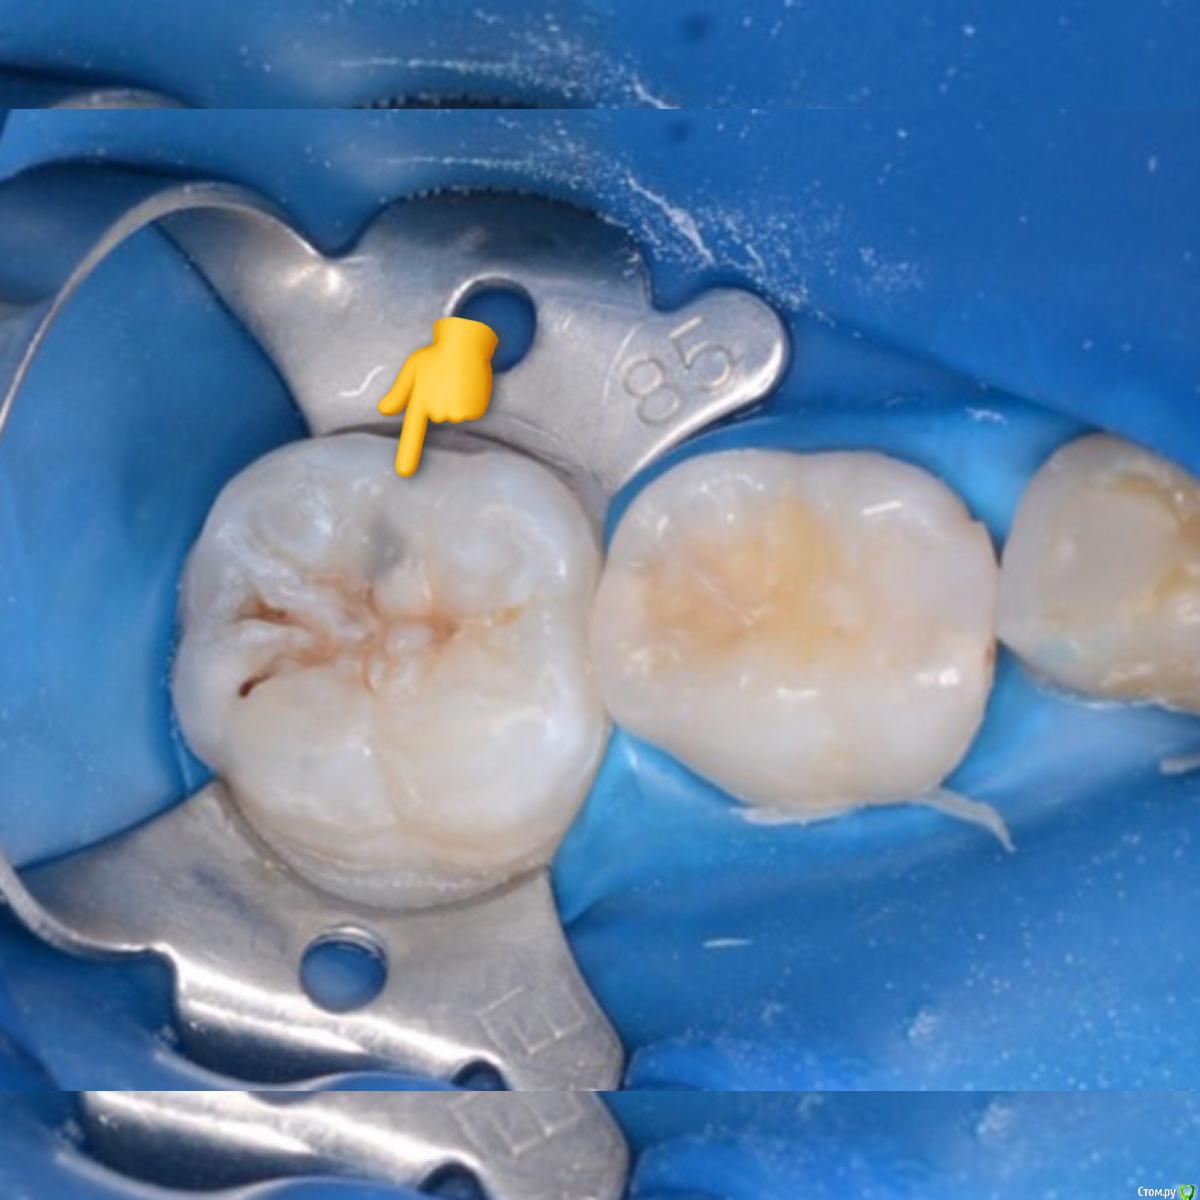

CRAZYDUCK Опубликовано 3 мая, 2018 Автор Поделиться Опубликовано 3 мая, 2018 Просто кариесули 7.4 и 7.5Обязательно убираем миловидную эмаль по контактам ( красной стрелкой на 7.5 указала )Обратите внимание , что rvg практически не визуализирует кариес медиально на 7.5 6 Ссылка на комментарий